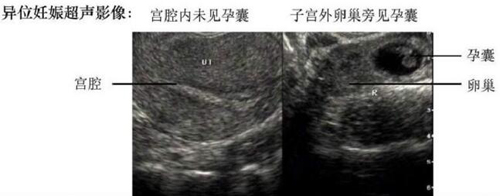

医生通常情况下需要通过妇科检查、血HCG、超声、穿刺等方法来进行综合判断和诊断。